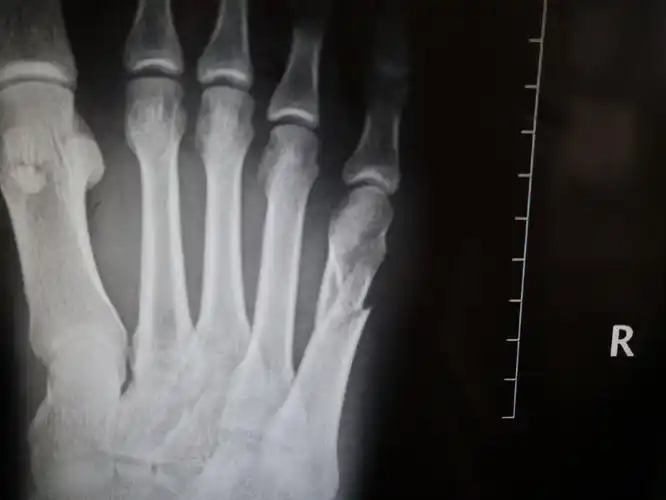

左足第三趾骨中节骨折两年余伴行走疼痛